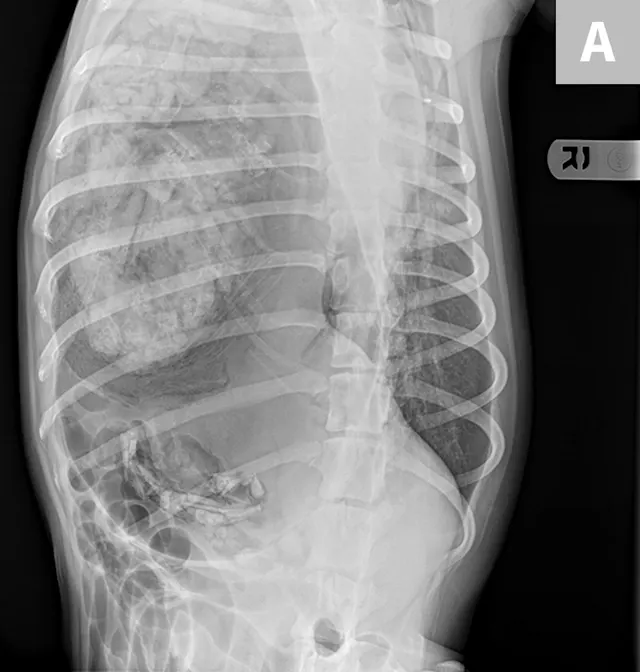

FIGURE 5A

(A) Dorsoventral and (B) right lateral radiographs of a 1-year-old spayed dog with acute-onset respiratory distress resulting from gastric dilatation in the left pleural cavity. The dog had a history of trauma approximately 1 month before presentation. The stomach is dilated, and a large amount of gas and food content can be seen in the left hemithorax